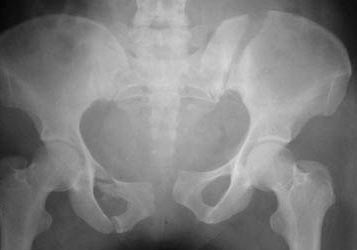

Ilium Fractures